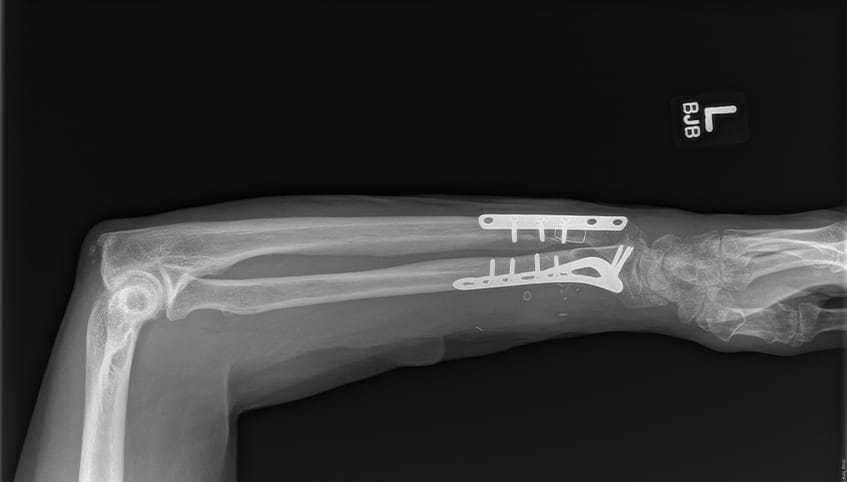

A surgical team performed an intricate 8-hour microsurgery to reattach Steve's forearm. Having completed fellowships in hand and upper extremity surgery, and addressing traumatic injuries such as this on a weekly basis, the team offered some of the region's best care in replantation and functional recovery.

Surgeons performed Steve's surgery under a microscope. They first plated and screwed the severed bones into place and then used sutures finer than a human hair to reconnect transected nerves, veins, blood vessels and tendons.